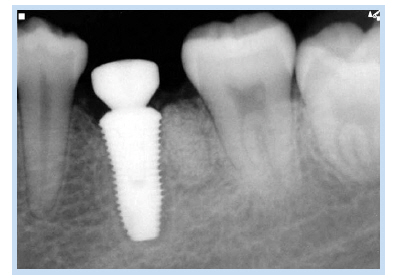

69세 여자 환자가 하악 좌측 제1, 2대구치 상실로 인한 저작의 어려움을 주소로 내원하였다. 하악 좌측 제1, 2대 구치는 6년 전 발치된 상태였고, 하악 좌측 제1대구치의 치근이 잔존해 있는 상태였다(Fig. 1). 내원하기 1개월 전 하악 좌측 제1대구치 부위에 통증이 있었다고 하였지만, 내원 시에는 통증이 없는 상태였다. 심장센터에서 부정맥 치료 중인 환자로 하악 좌측 제1대구치 잔존 치근을 발거하고 하악 좌측 제1, 2대구치 부위에 임플란트를 식립하기로 계획하였다. #46 잔존 치근을 발거하고 치조정 절개를 가하여 피판을 거상한 후 임플란트 drilling을 시행하였다. 그 후 하악 제1대구치에 직경 4.8 mm, 길이 1.5 mm의 임플란트, 하악 제2대구치에 직경 4.8 mm, 길이 10 mm의 임플란트를 일회법으로 식립(Osstem SS II; Osstem Implant, Seoul, Korea)하였다. 치유 지대주(healing abutment)를 연결 후 피판을 재위치시키고 4-0 Vicryl (Johnson & Johnson, New Brunswick, NJ, USA)로 봉합하였다. 임플란트 식립 1주일 후 봉합사를 제거하고 파노라마 방사선 사진과 치근단 방사선 사진을 촬영하였다. 이때 #36 부위에 원심 치근으로 추정되는 방사선 불투과상이 관찰되었으나 감염 등 특별한 증상이 없었고 잔존 치근을 무리하게 제거한다면 그로 인한 골소실 및 임플란트 골유착에 오히려 방해가 될 수 있다고 판단하여 잔존시킨 상태에서 정기적 관찰을 결정하였다(Fig. 2, 3). 임플란트 식립 2개월 후 최종 보철물이 장착되었으며 임플란트 식립 후 115개월간의 치근단 방사선 사진을 통한 경과 관찰 시 안정적으로 임플란트가 유지되고 있음을 관찰할 수 있었다(Fig. 4, 5).

Fig. 3. Periapical radiograph 1 week after implant placement. This radiopaque image was considered as remained root.

Jun-Bae Sohn et al. : Implant Placed in Contact with Retained Root: Case Reports. Implantology 2016